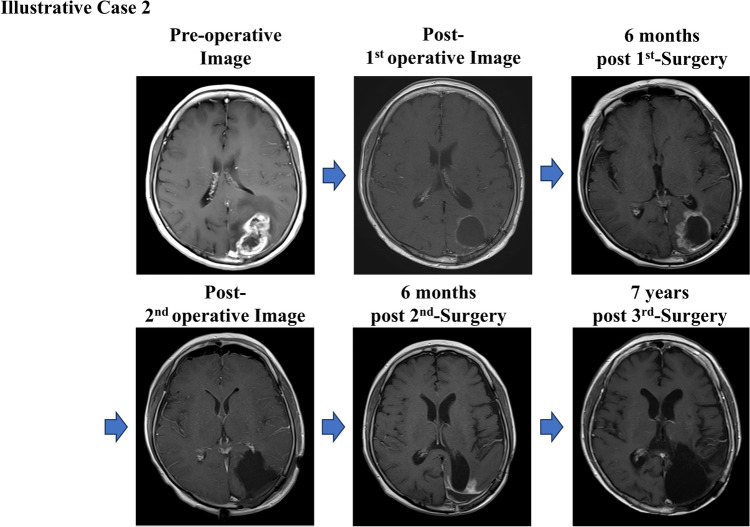

Abstract Image